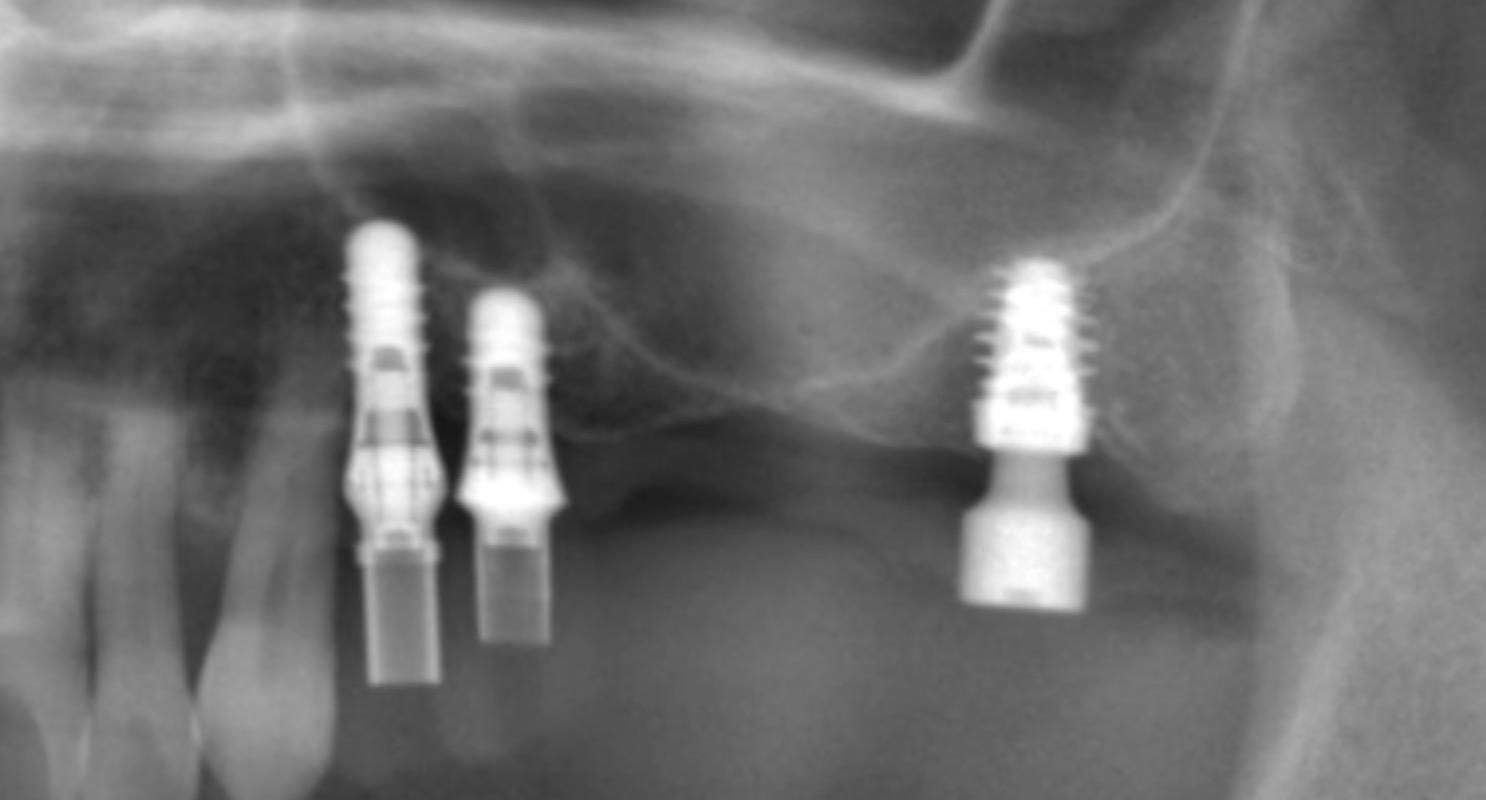

そのような場合に、このようにバイコルチカルの埋入は1つの選択肢となります。

本症例は今回└7を追加しましたが、インプラント部のHU値は190と弱い骨質であることが分かっていました。

そこで、バイコルチカルな埋入で対応させて頂いております。バイとは、歯槽骨と上顎洞底骨で固定すると

いうことです。歯槽骨は言い方を悪くするとスカスカなのですが、上顎洞庭骨は硬いので、必ずではないですが

あたったら感覚で分かります。最近では上顎洞穿孔のリスクを減らすため、このような埋入もサージカルガイドを

用いて行います。

本症例は└45も骨質が弱くバイコルチカルとしており、現在プロビジョナルはとても経過がいいです。

本症例は└6相当部は骨がなくインプラント埋入が不可能です。サイナスグラフトをする方法もありますが、

コストと侵襲が大きくなるため、このような埋入をするプランを立案し、プラン通り終わっております。